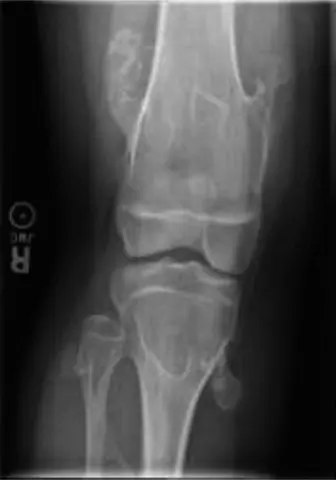

تظهر النابتات بشكل متكرر في العظام الطويلة، خاصةً حول الركبتين (نهاية عظم الفخذ القريبة ونهاية الظنبوب القريبة) وحول الكوع (نهاية عظم العضد البعيدة ونهاية الزند والكعبرة القريبة). ومع ذلك، يمكن أن تظهر في أي عظم غضروفي التكوين، بما في ذلك:

الأشعة السينية (X-rays):

- هي الخطوة التشخيصية الأولية والأكثر شيوعاً.

- تُظهر النابتات العظمية بوضوح كبروزات عظمية تنشأ من قشرة العظم، مع استمرارية في نخاع العظم الأصلي.

- تساعد في تقييم عدد النابتات، مواقعها، حجمها، واتجاه نموها.

- تُستخدم أيضاً لمراقبة تطور النابتات وتشوهات النمو العظمي مع مرور الوقت.